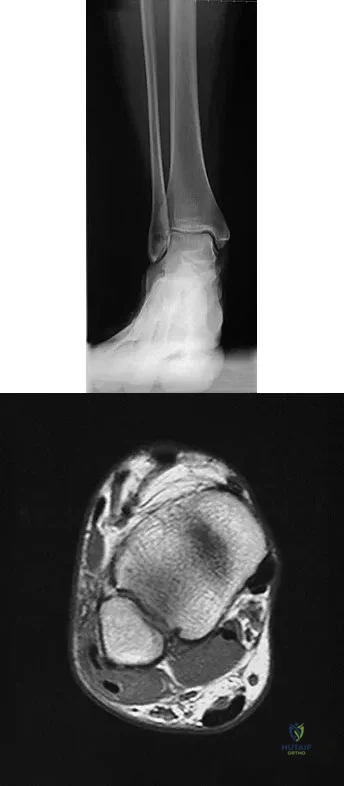

Figures 25a and 25b show the radiograph and MRI scan of a 7 1/2-year-old boy who has been limping for 1 year. His pain has worsened over the past 2 weeks, and his parents note swelling over the dorsum of the foot for the past 4 days. Examination reveals no fever, and laboratory studies show a WBC of 6,700/mm3, an erythrocyte sedimentation rate of 26 mm/h, and a normal C-reactive protein level. What is the most likely diagnosis?

Explanation